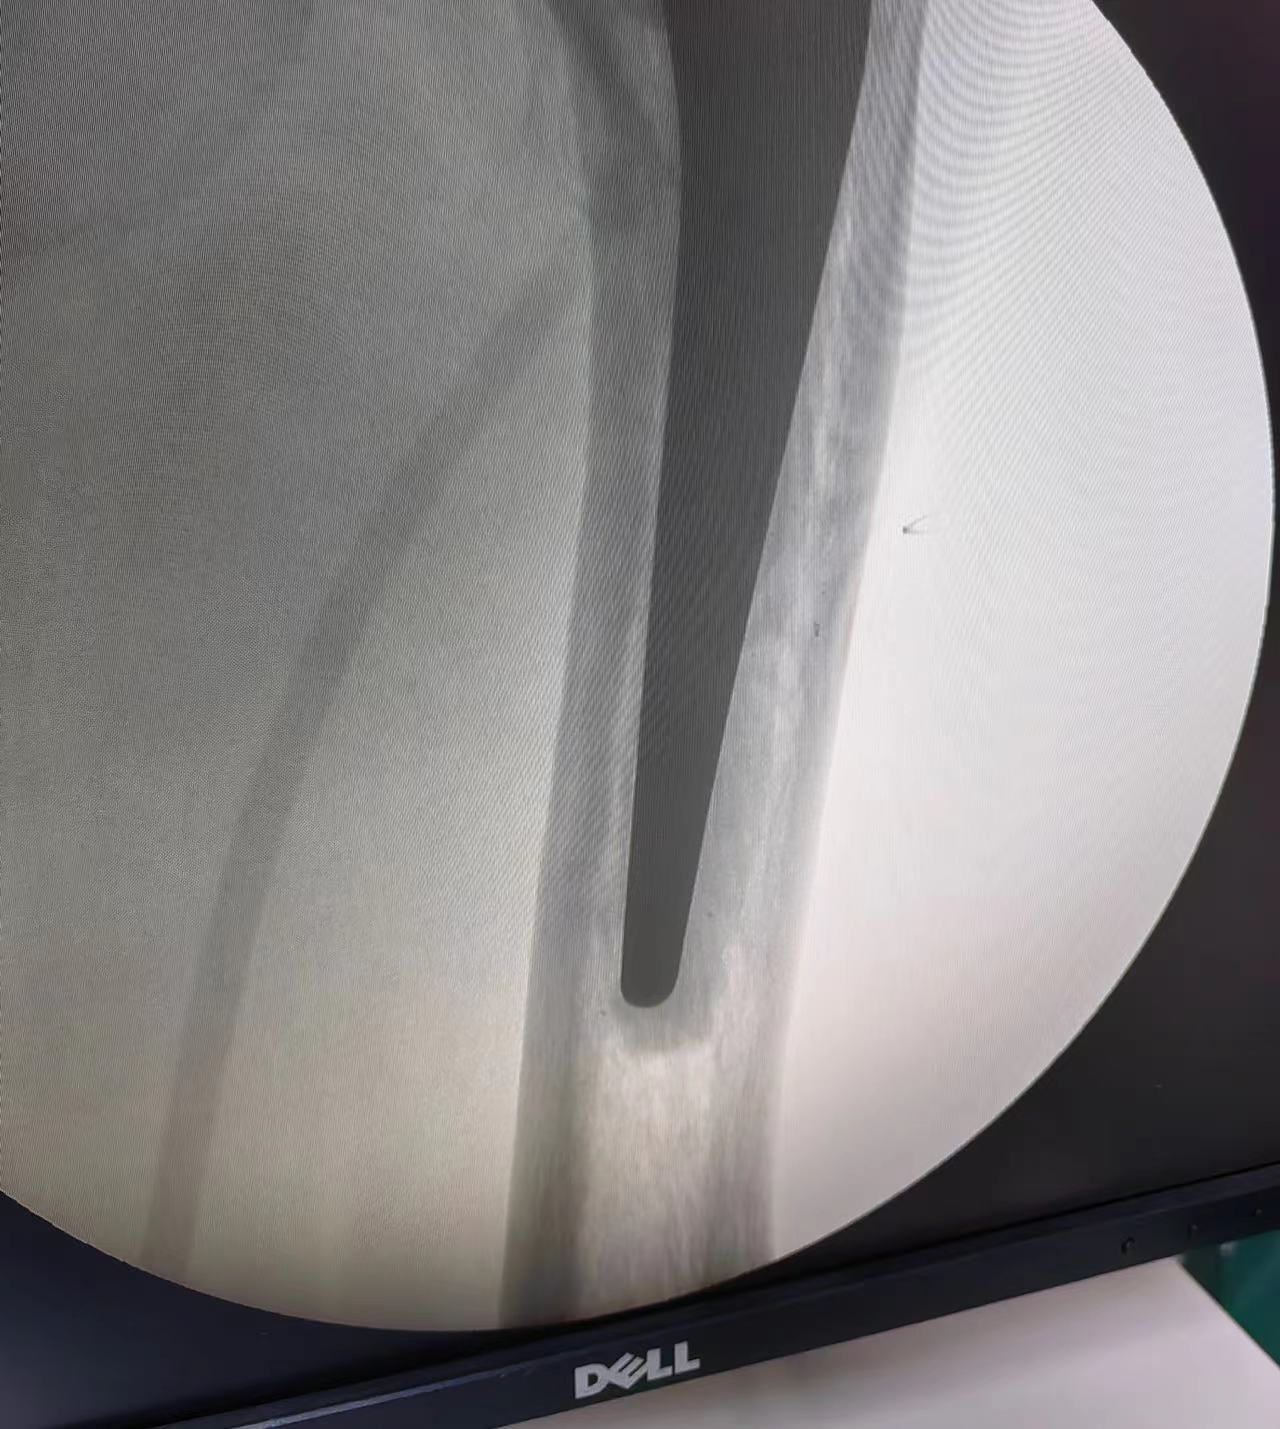

今日,我院一位90岁高龄髋关节置换患者康复出院。蚌埠市康复医院(市四院)李叶刚副院长带领骨科医护人员,一早来到病房看望患者。患者,女,90岁高龄,因摔伤导致“左股骨粗隆间骨折”入院,医院骨科团队给予髋关节置换手术治疗。术后3天,患者在康复师的指导帮助下开始床边站立锻炼。术后第7天,主管医生详细交代出院康复锻炼方法,及其他注意事项后,患者出院回家休养。

高龄患者粗隆间骨折以粉碎性居多,大小粗隆及外侧壁粉碎破裂,且伴有不同程度的骨质疏松。保守治疗需长期卧床,易发生下肢深静脉血栓、压疮、坠积性肺炎、泌尿系统感染等并发症,加之老年人基础疾病较多,长期卧床保守治疗的病死率可高达34%,被称为“人生最后一次骨折”。因此针对粗隆间骨折,在身体条件允许的情况下,尽可能早期手术治疗,传统内固定手术可以满足床上早期康复锻炼,但不能早期下床活动。采用髋关节置换治疗该类患者,可以满足患者早日下床活动及早期康复需要。